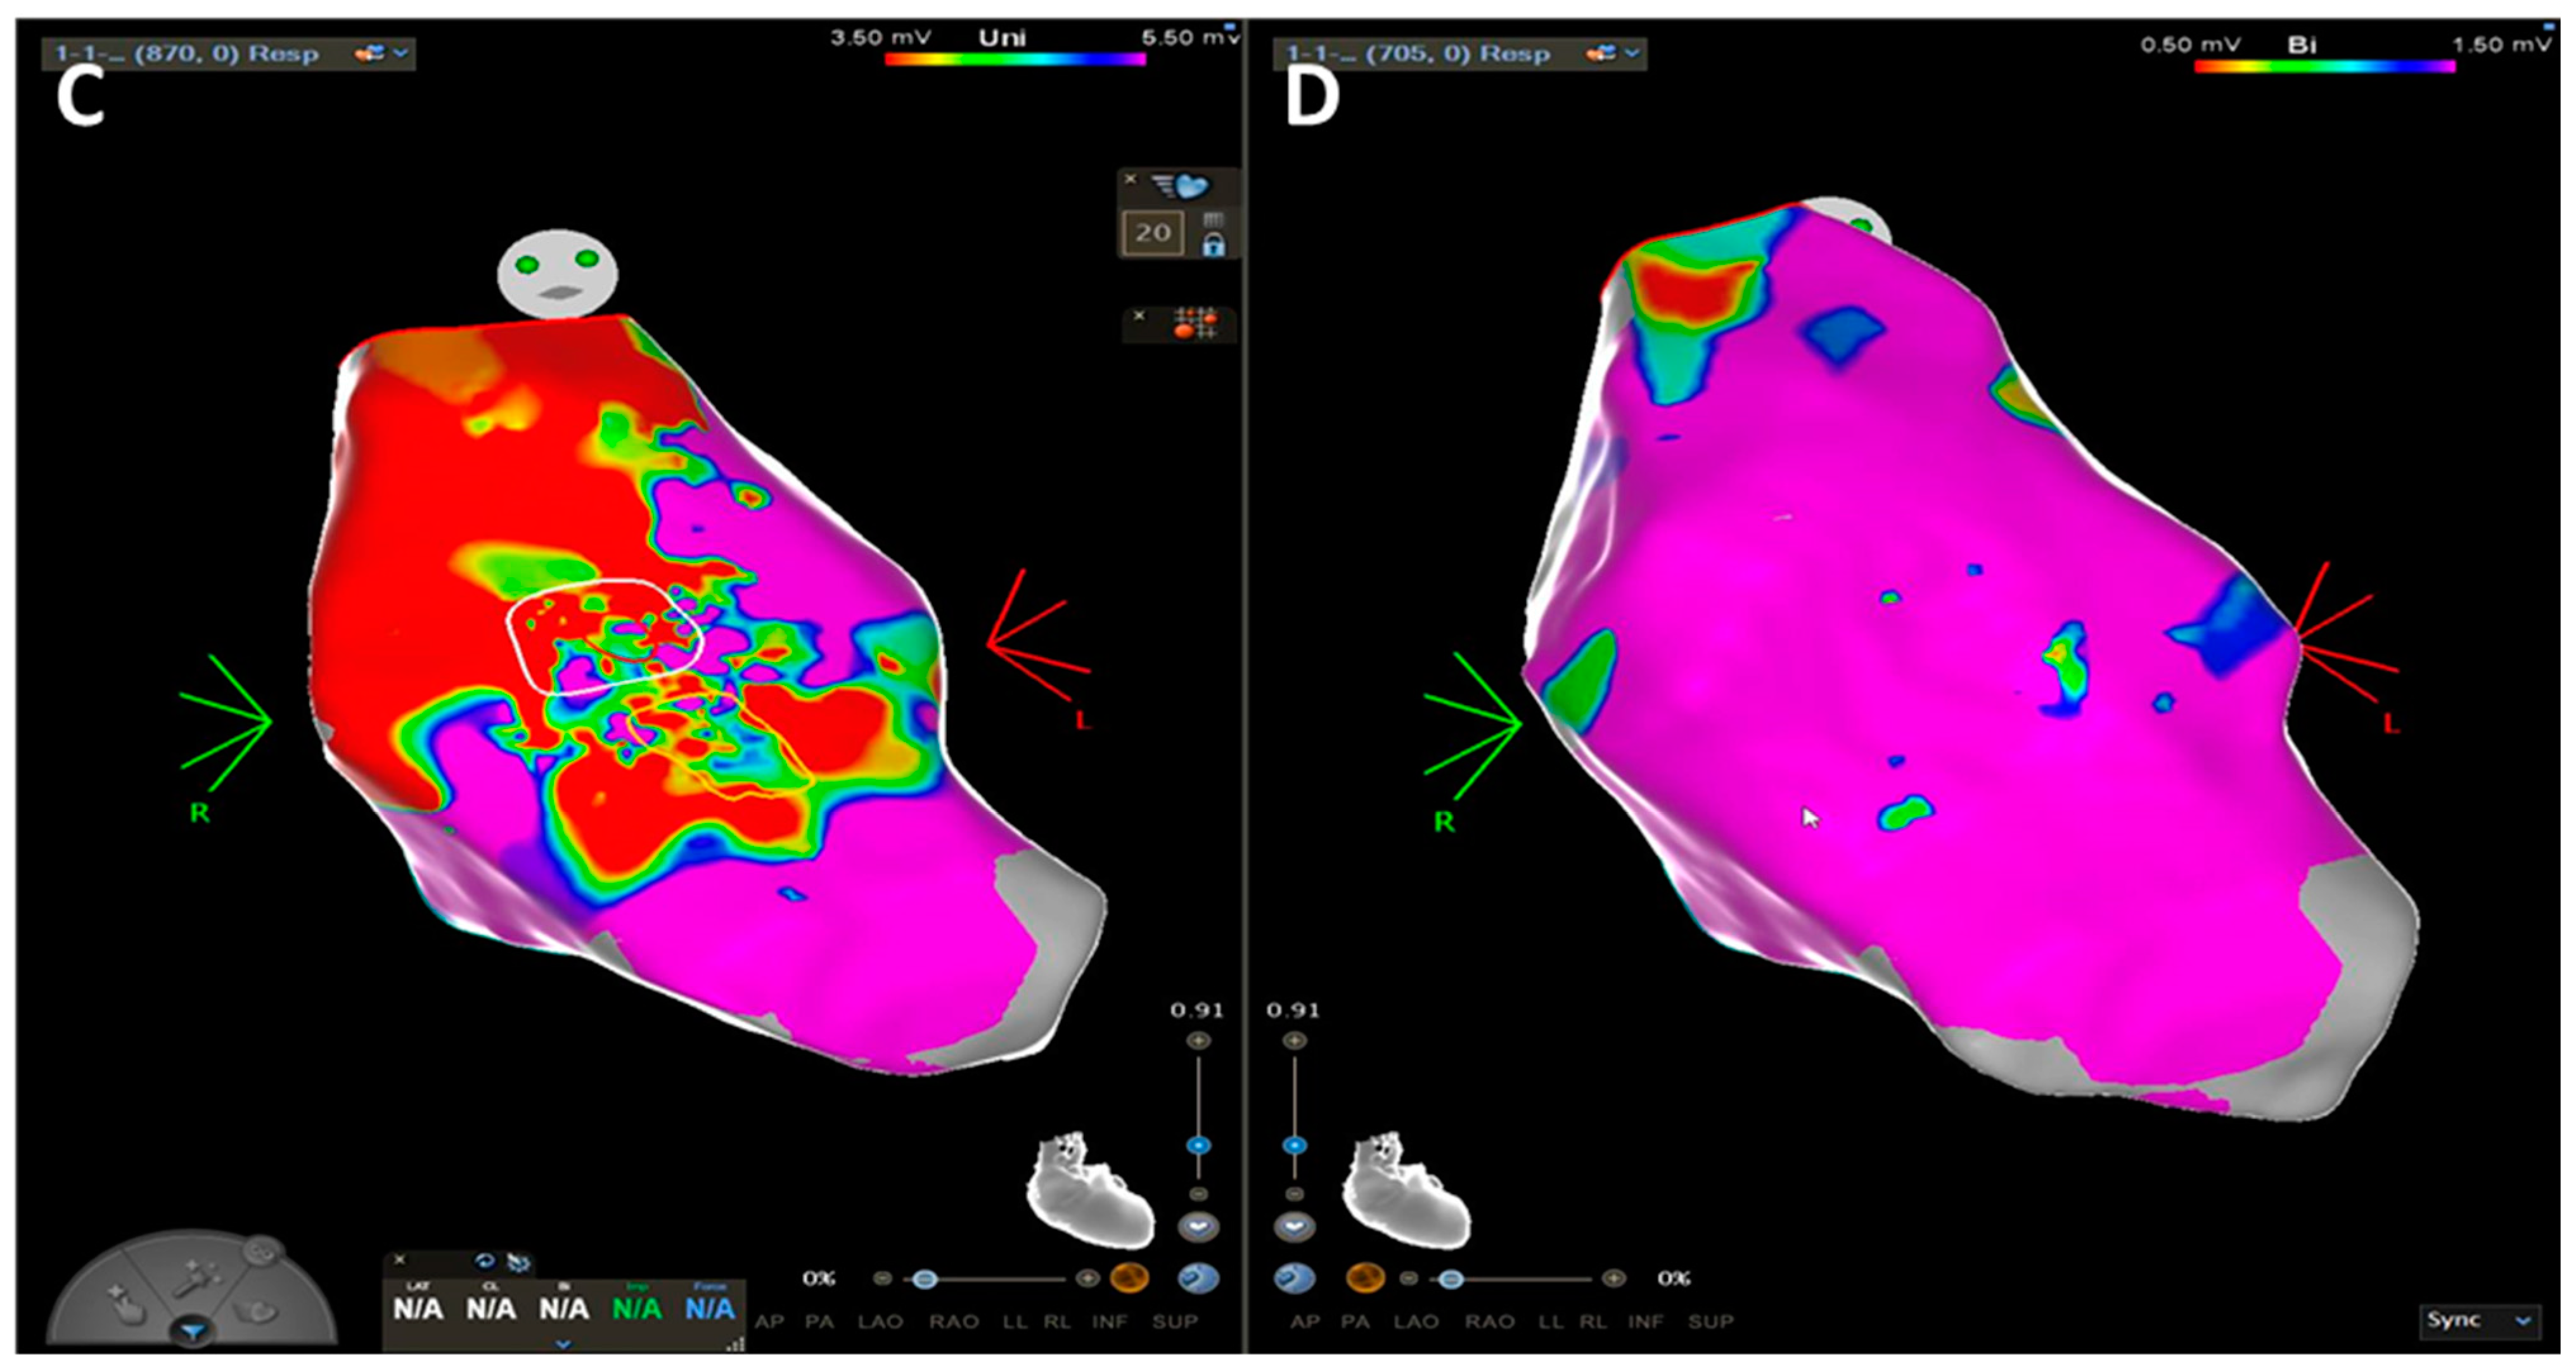

3. The World of ACM and DCM: How “Complex Imaging” (Electroanatomic Mapping) Directs Diagnosis and Invasive Management

3.1. Arrhythmogenic Cardiomyopathy

3.2. Dilated Cardiomyopathy